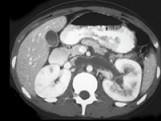

男,48岁,蛋白尿多年,CT如图所示,诊断为肾静脉血栓,肾静脉血栓形成的原因 ( )A.膜性肾小球肾炎B.肾癌C.胰腺炎D.外压性...

问题 男,48岁,蛋白尿多年,CT如图所示,诊断为肾静脉血栓,肾静脉血栓形成的原因 ( )

选项 A.膜性肾小球肾炎 B.肾癌 C.胰腺炎 D.外压性 E.创伤、脱水、血小板增多症

答案 ABCDE